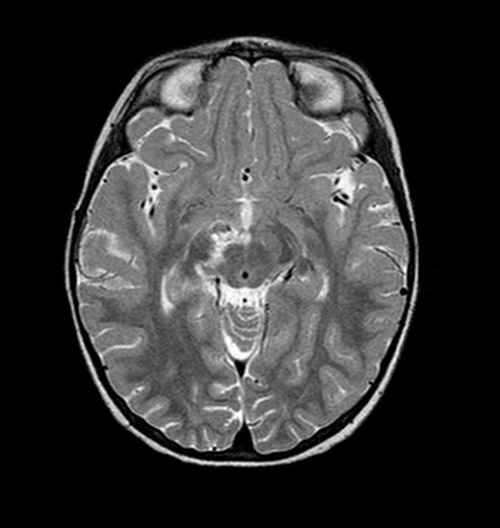

A los 15 días de ingreso, se repite el estudio de imagen, que muestra una disminución significativa de las lesiones descritas en el troncoencéfalo, el hipocampo y el tálamo, con desaparición de la afectación del pálido y tracto óptico retroquiasmático derecho, hallazgos compatibles con encefalitis viral evolucionada.